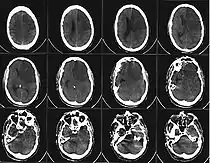

![]() Компьютерная томограмма головного мозга, демонстрирующая инфаркт в правом полушарии головного мозга (зона инфаркта обведена красным.) | |